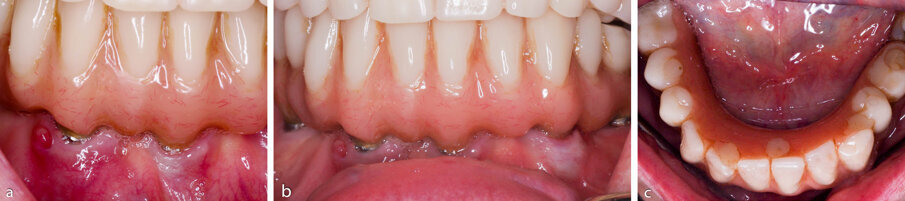

Figure 2a-c. Pre-operative clinical photographs.

The following case study illustrates a protocol that was used to treat advanced peri-implantits. The case was treated successfully with a 6-month follow-up. Success was defined by a reduction in probing pocket depths (≤4mm), along with a reduction of soft tissue redness and bleeding on probing.

A 70-year-old female was referred for advanced peri-implantitis in the mandible. She presented complaining of pain and she also noticed discharge from one of the anterior implants. Her medical history was non-contributory and she was a non-smoker.

Clinical examination revealed 5 implants in the mandible supporting a fixed full arch reconstruction. Probing pocket depths were of the order of 8-9mm around 3 of the anterior implants. The distal implants had normal probing depths. CBCT imaging revealed an intrabony component of 6.1mm for the implant in the 43 position, 4.2mm at the 41 implant and 3.1 at the 33 implant.